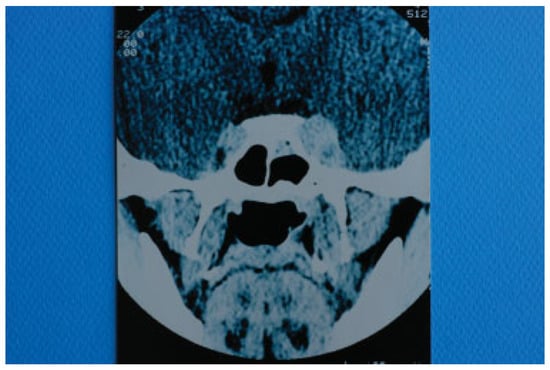

Figure 3. Computed tomography of the skull taken with intravenous contrast medium. Dilation of left superior ophthalmic vein is depicted.

On the 21st postoperative day (31st postinjury day), the patient presented with marked left exophthalmos, periorbital swelling and ecchymosis, ptosis of the upper eyelid, ocular pain, nausea, and vomiting. The condition was diagnosed as periorbital cellulitis and double intravenous antibiotic therapy was initiated (Figure 2). Computerized tomography (CT) of the left orbit disclosed a mild inflammatory reaction around the miniplate in the infraorbital rim and in the region of the orbital floor. CT also revealed the presence of dilation of the upper ophthalmic vein but this finding was not further evaluated at that time (Figure 3). The clinical presentation of the patient was attributed to infection of foreign materials that were placed during the operation and therefore the plate and the lyophilized dura were removed.